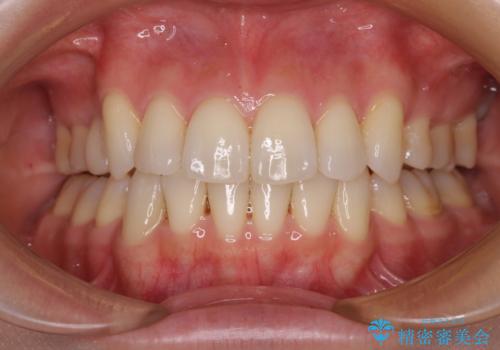

- 50代男性

- 奥歯が割れてしまい、抜歯が必要となった患者様です。

以前にも歯が割れてインプラント治療を行いましたが、抜歯してからインプラント埋入→仮歯装着までに半年以上を要し、その間に残された歯への負担が大きくなり、セラミッククラウンが破折したことがありました。